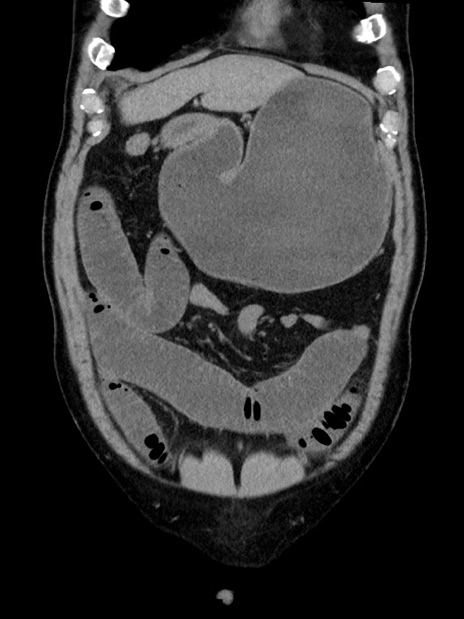

症例35(冠状断像)

【症例】70歳代 男性

【主訴】腹部膨満、嘔吐

【現病歴】昨日より腹部膨満感出現。本日増悪し、仙痛出現。嘔吐あり、受診。

【既往歴】糖尿病、胆摘後

【身体所見】BP 149/80mmHg、HR 74/min、BT 35.9℃、腹部:膨満、軟、圧痛なし。腸雑音減弱あり。上腹部正中切開瘢痕あり。

【データ】WBC 13500、CRP 1.72